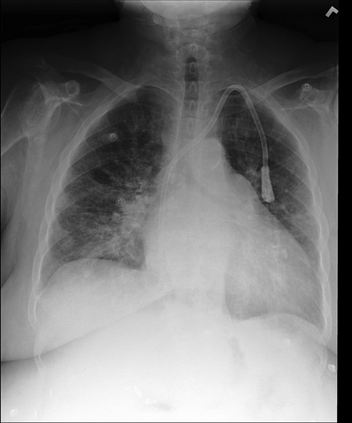

The latest breakthroughs in large vision-language models, such as Bard and GPT-4, have showcased extraordinary abilities in performing a wide range of tasks. Such models are trained on massive datasets comprising billions of public image-text pairs with diverse tasks. However, their performance on task-specific domains, such as radiology, is still under-investigated and potentially limited due to a lack of sophistication in understanding biomedical images. On the other hand, conversational medical models have exhibited remarkable success but have mainly focused on text-based analysis. In this paper, we introduce XrayGPT, a novel conversational medical vision-language model that can analyze and answer open-ended questions about chest radiographs. Specifically, we align both medical visual encoder (MedClip) with a fine-tuned large language model (Vicuna), using a simple linear transformation. This alignment enables our model to possess exceptional visual conversation abilities, grounded in a deep understanding of radiographs and medical domain knowledge. To enhance the performance of LLMs in the medical context, we generate ~217k interactive and high-quality summaries from free-text radiology reports. These summaries serve to enhance the performance of LLMs through the fine-tuning process. Our approach opens up new avenues the research for advancing the automated analysis of chest radiographs. Our open-source demos, models, and instruction sets are available at: https://github.com/mbzuai-oryx/XrayGPT.